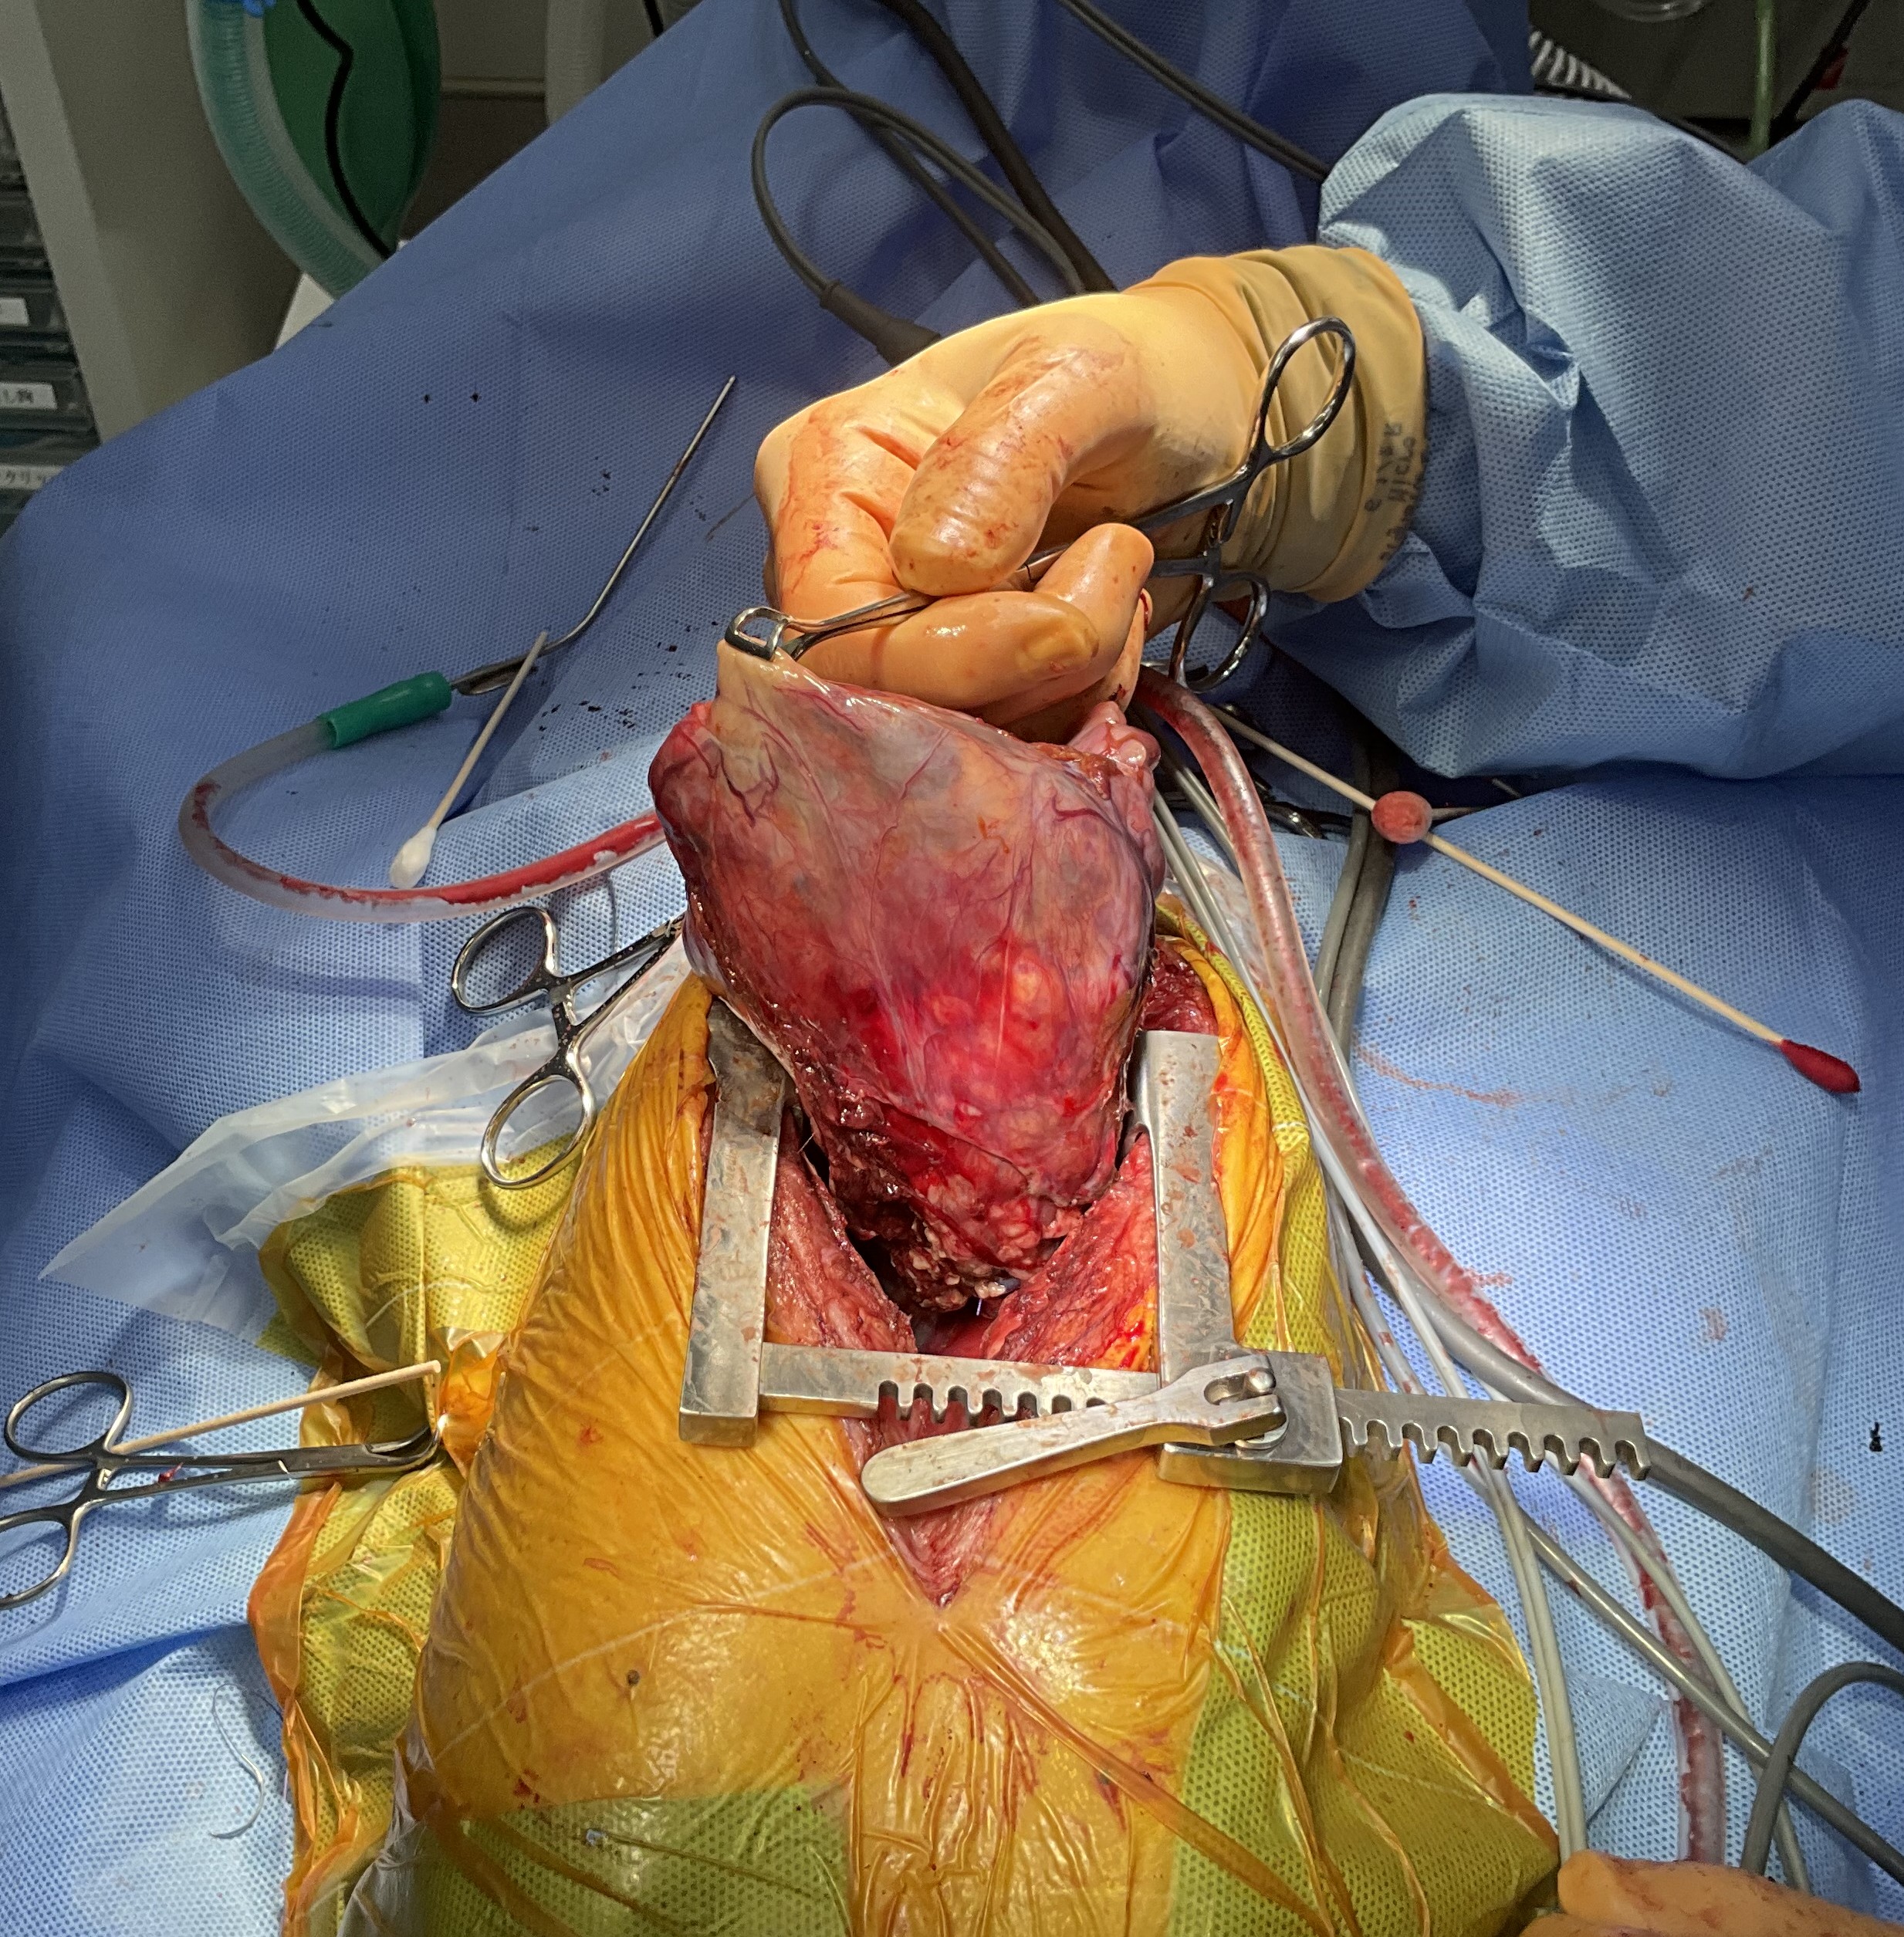

前胸部腫瘤摘出手術

胸骨を切開すると、前胸部に大きな腫瘤(白丸)が肉眼的に確認できました。

腫瘤に流入する血管は一本一本丁寧に処理しました。

胸腔内から腫瘤を取り出す瞬間です。